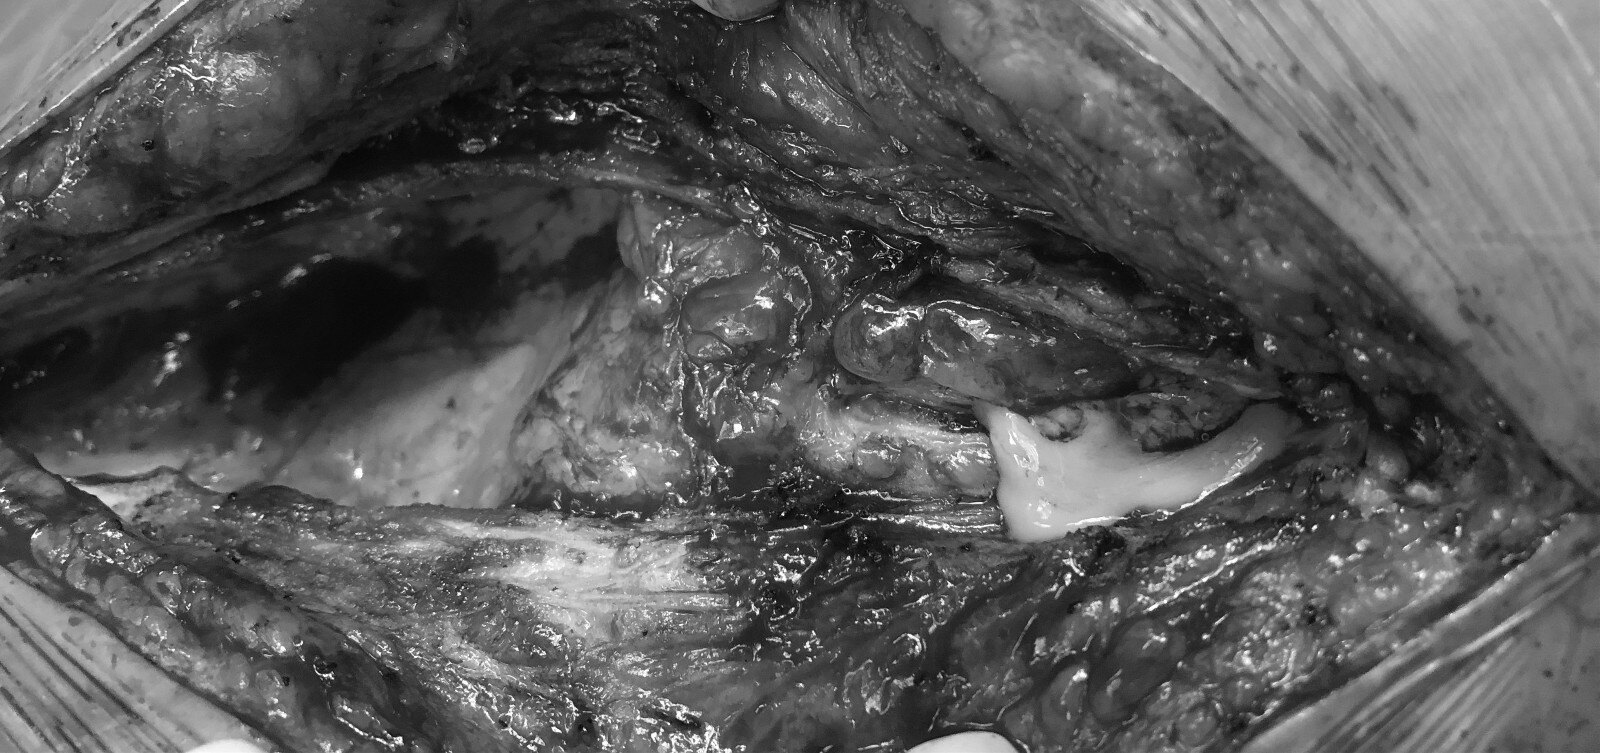

肾囊肿术后窦道形成伴感染经久不愈一例